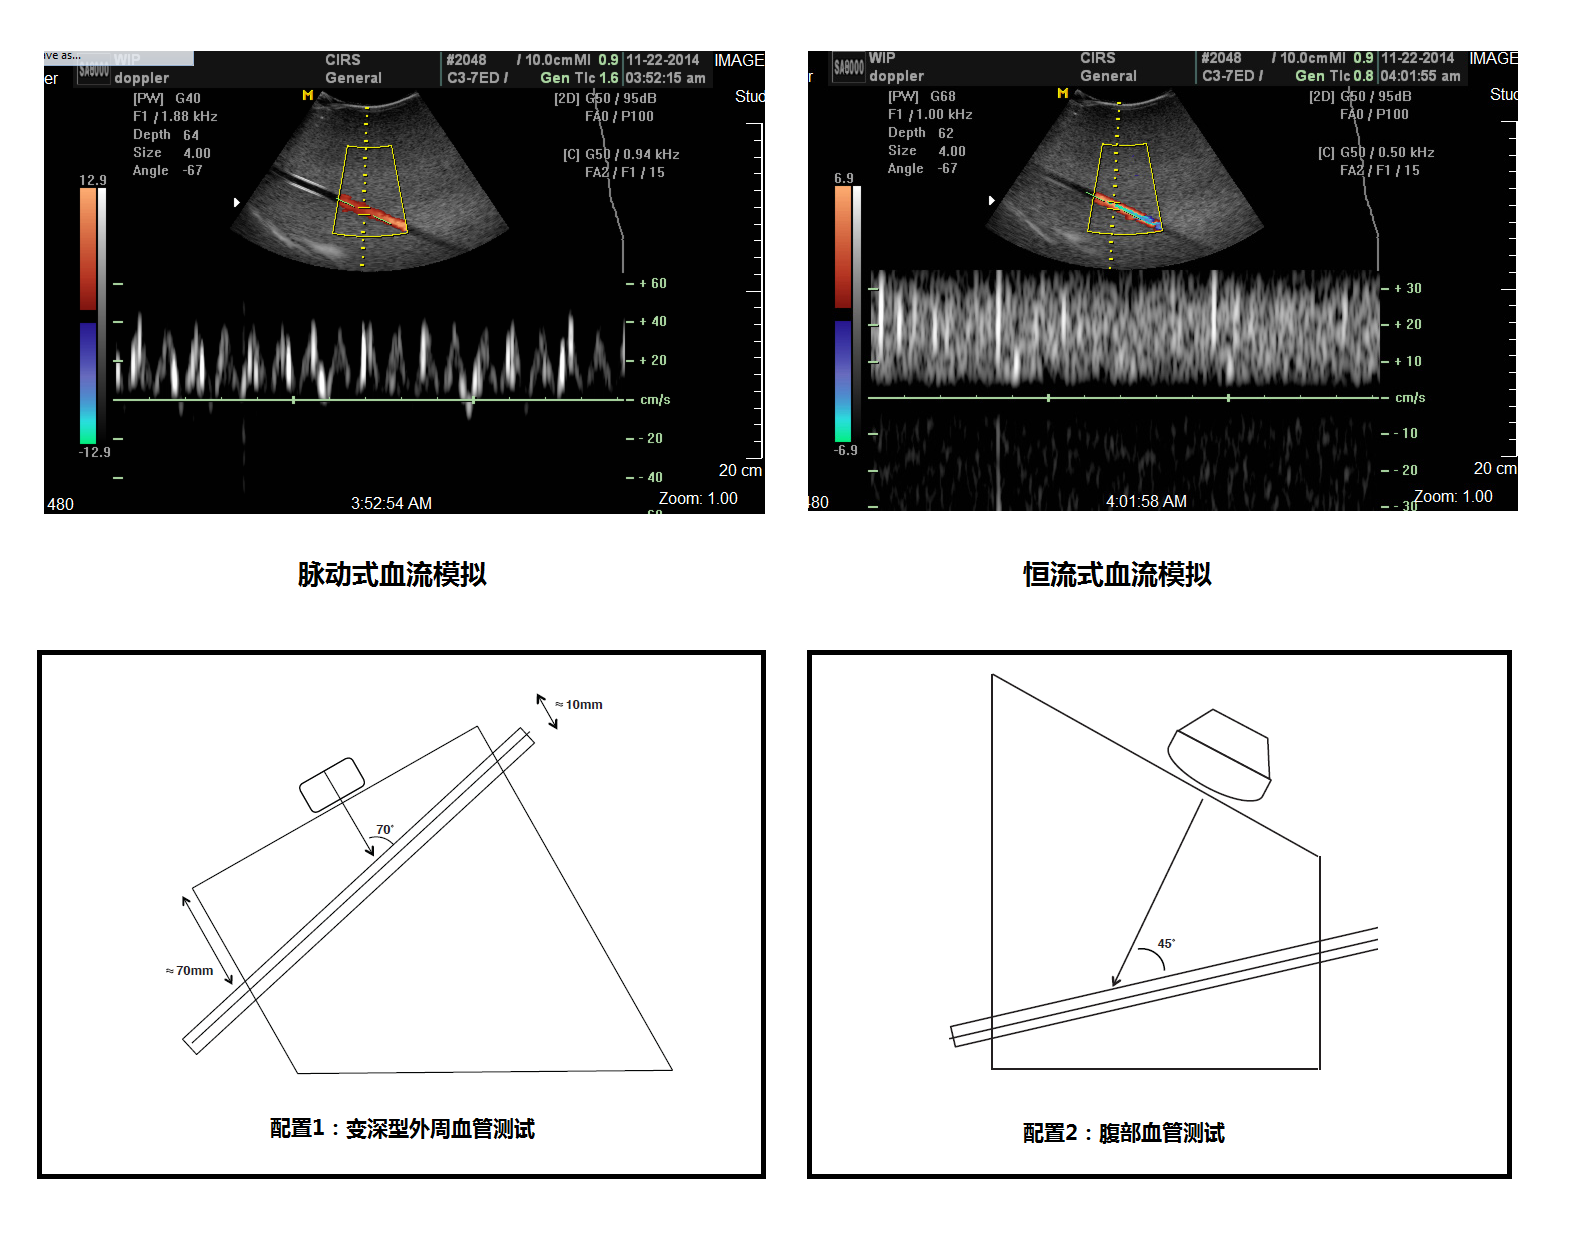

超聲多普勒流量模擬機(jī)是專門為了在仿真組織內(nèi)模擬血流量的模體,可以使用在測(cè)量超聲多普勒儀器的質(zhì)量檢測(cè)應(yīng)用之中。常用的兩個(gè)測(cè)試為靈敏度和速度準(zhǔn)確性,除此之外還可以應(yīng)用在其他幾個(gè)測(cè)試,詳情請(qǐng)察看相關(guān)附件。

模擬機(jī)包含一個(gè)仿真流量模體,一條模擬血管的超聲配用導(dǎo)管斜插在模體之中。模體頂部和底部均設(shè)有掃描表面,提供不同深度和角度的應(yīng)用需要。這樣的設(shè)計(jì)充分發(fā)揮模體的靈活性來測(cè)試皮表掃描和深度腹腔血管的掃描的需求。

3.脈沖流和均速流兩種選擇

5.漸變深度,表層和腹腔血管模擬

模塊1    內(nèi)置血管1條,夾角45°70°,血管內(nèi)徑3/16in,模擬腹部血管,外周血管